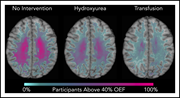

Hydroxyurea reduces cerebral metabolic stress in patients with sickle cell anemia

Melanie E. Fields,Kristin P. Guilliams,Dustin Ragan,Michael M. Binkley,Amy Mirro,Slim Fellah,Monica L. Hulbert,Morey Blinder,Cihat Eldeniz,Katie Vo,Joshua S. Shimony,Yasheng Chen,Robert C. McKinstry,Hongyu An,Jin-Moo Lee,Andria L. Ford